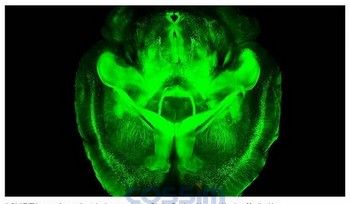

科學(xué)家為了更清楚標(biāo)記大腦內(nèi)不同分子,以加強研究準(zhǔn)確度,使用一項能使大腦透明的技術(shù),并使用光學(xué)顯微鏡來產(chǎn)生圖像。研究團隊先利用小老鼠的大腦模擬人類大腦,沒想到發(fā)現(xiàn)驚人結(jié)果,原來就算死后,人類大腦里的分子結(jié)構(gòu)都還是一樣,不會因外在因素改變而消失,這項技術(shù)也能用來預(yù)防更多疾病。

螢光綠色圖像(如下圖)中間有密密麻麻、一點一點的東西,這就是科學(xué)家為了找出人類死后腦部的分子活動是不是和生前一樣,利用最新技術(shù),使用光學(xué)顯微鏡經(jīng)過層層處理將人類大腦變成透明后所呈現(xiàn)出的圖像,圖中的綠點即為大腦內(nèi)的分子。

其實,科學(xué)家一開始是從小老鼠大腦先研究,經(jīng)過數(shù)百次失敗才成功,因為大腦要呈現(xiàn)透明并不是那么容易,必須經(jīng)過2天的凈度過程,腦部分子才會慢慢浮現(xiàn)出來??茖W(xué)家證實,老鼠死后的腦部分子結(jié)構(gòu)還是和生前一樣。